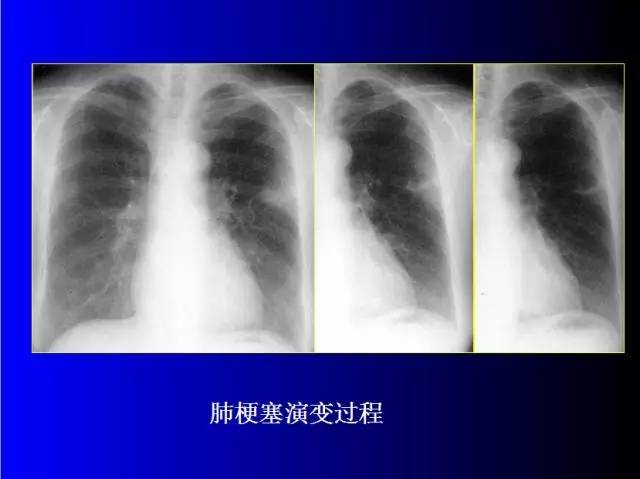

肺部基础X片及CT片解读